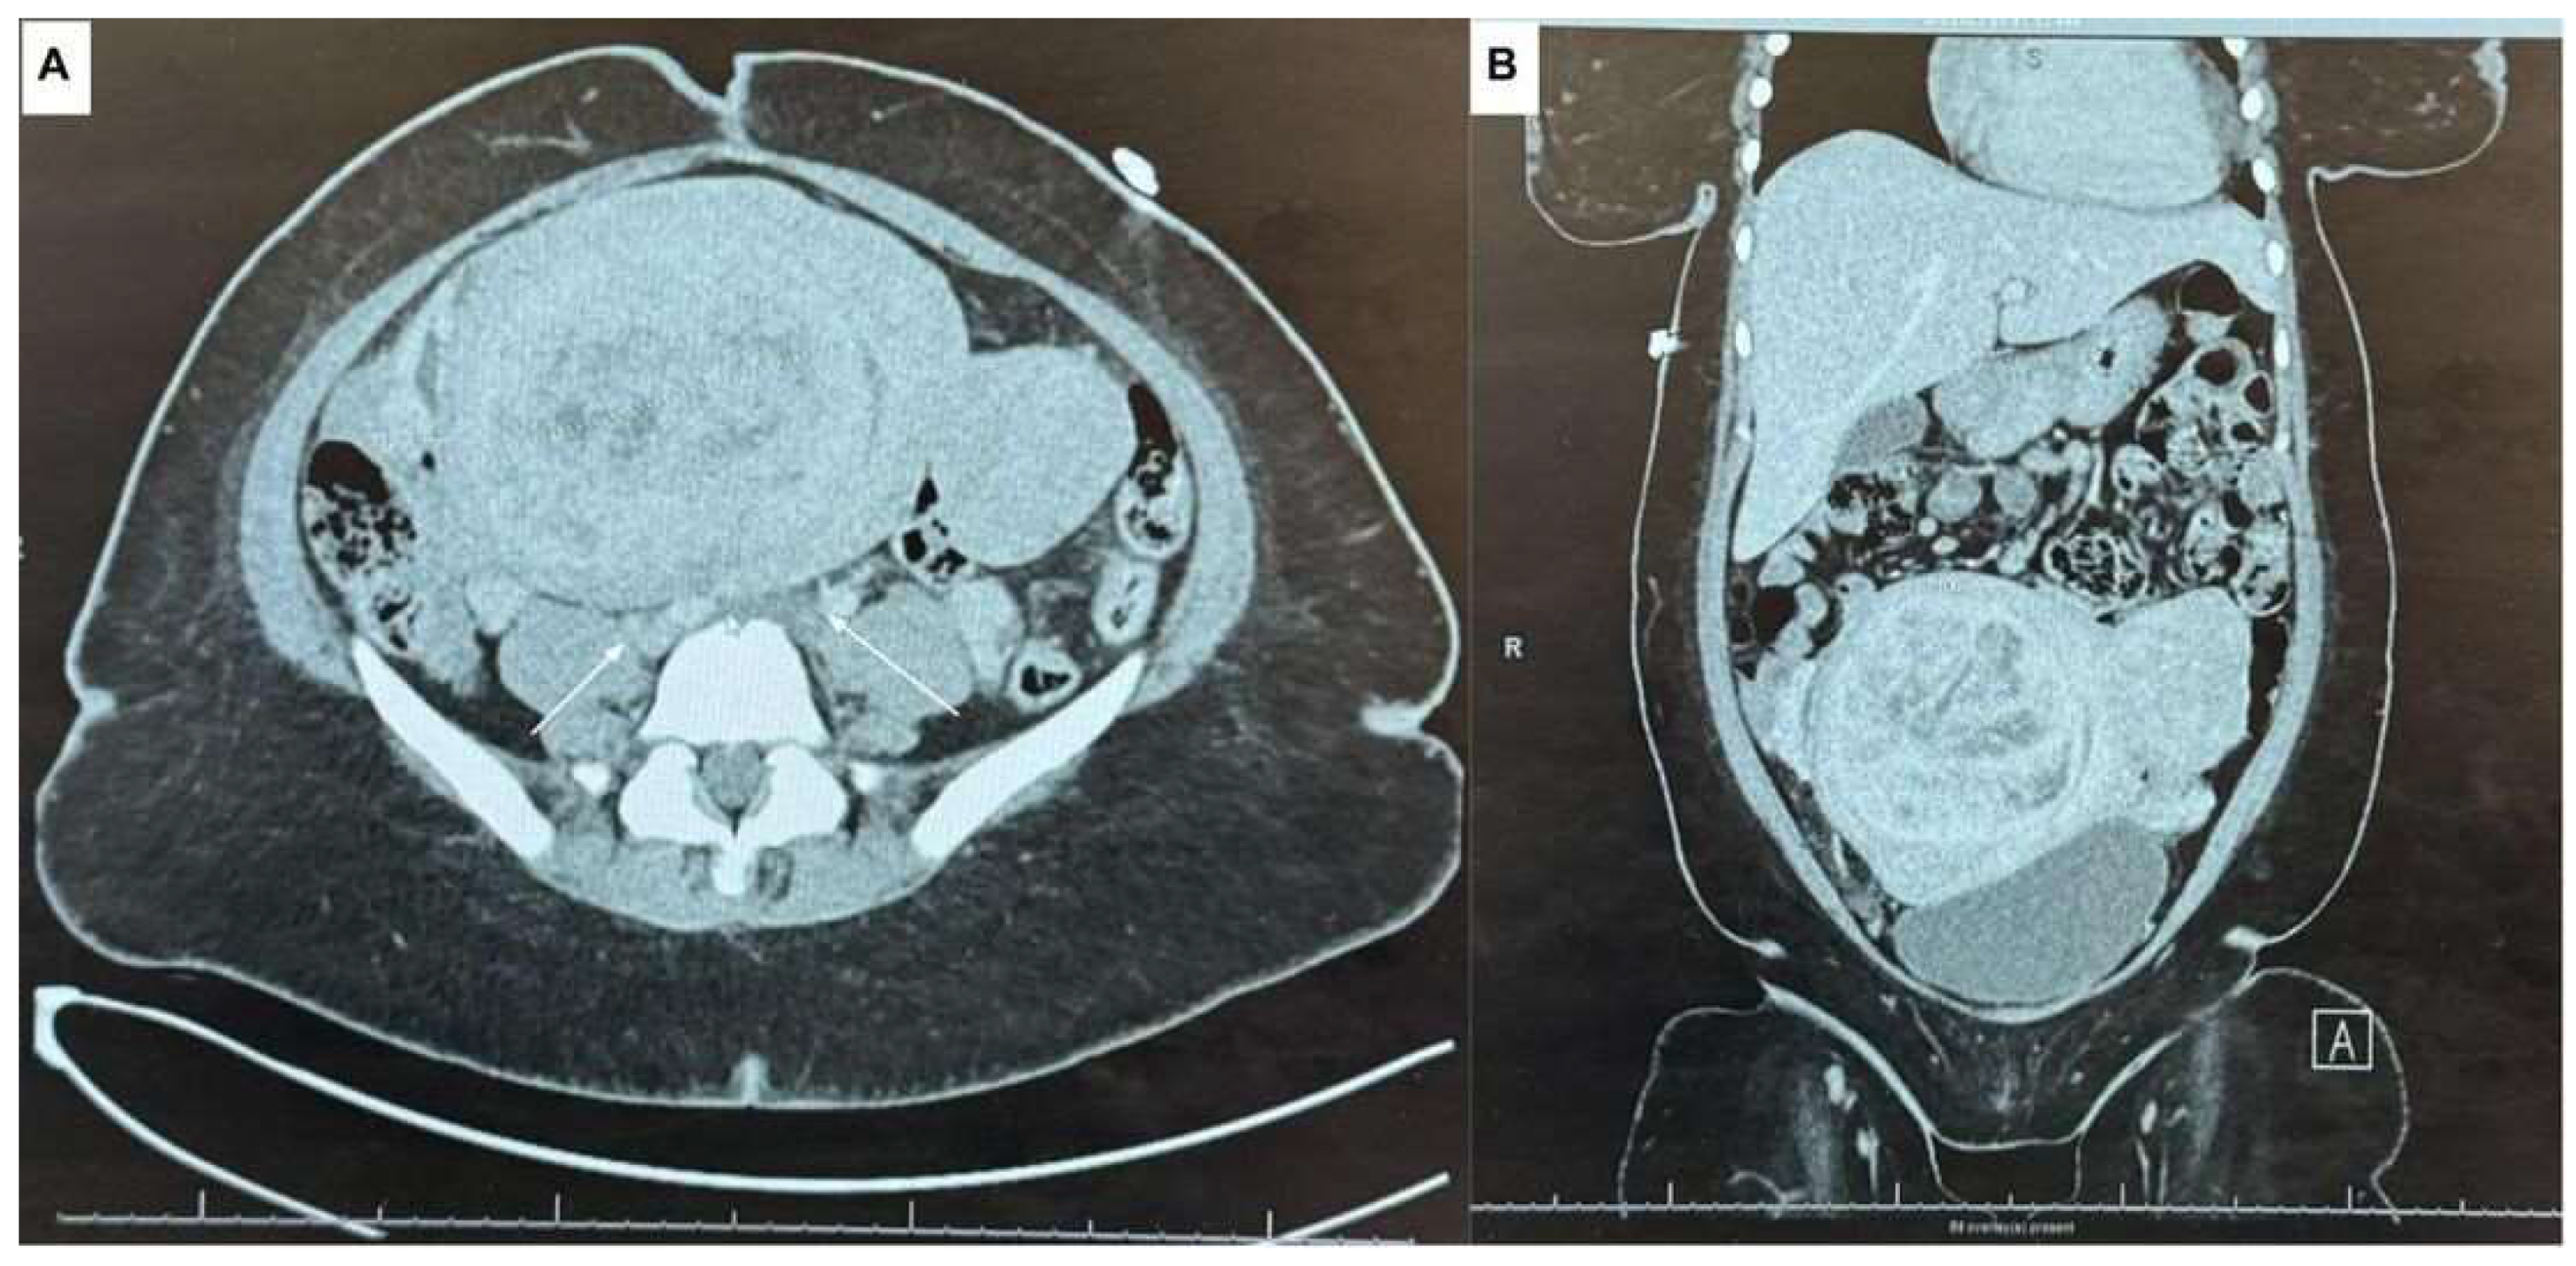

2. Case Presentation